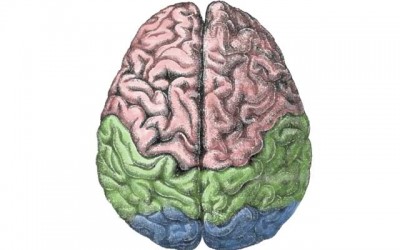

London, July 21 (IBNS): A clinical trial of the use of adrenaline in cardiac arrests has found that its use results in less than 1% more people leaving hospital alive - but almost doubles the risk of severe brain damage for survivors of cardiac arrest.

London, Sept 6 (IBNS) A gene has been identified by a joint study by researchers at King’s College London, Duke-NUS Medical School (Duke-NUS), Inserim and Paris Diderot University that is thought to be associated with the types of brain damage that can be caused by pre-term birth.

London, Mar 21 (IBNS): A small protein that could protect the brain from stroke-induced injury has been discovered by researchers from The University of Queensland and Monash University.